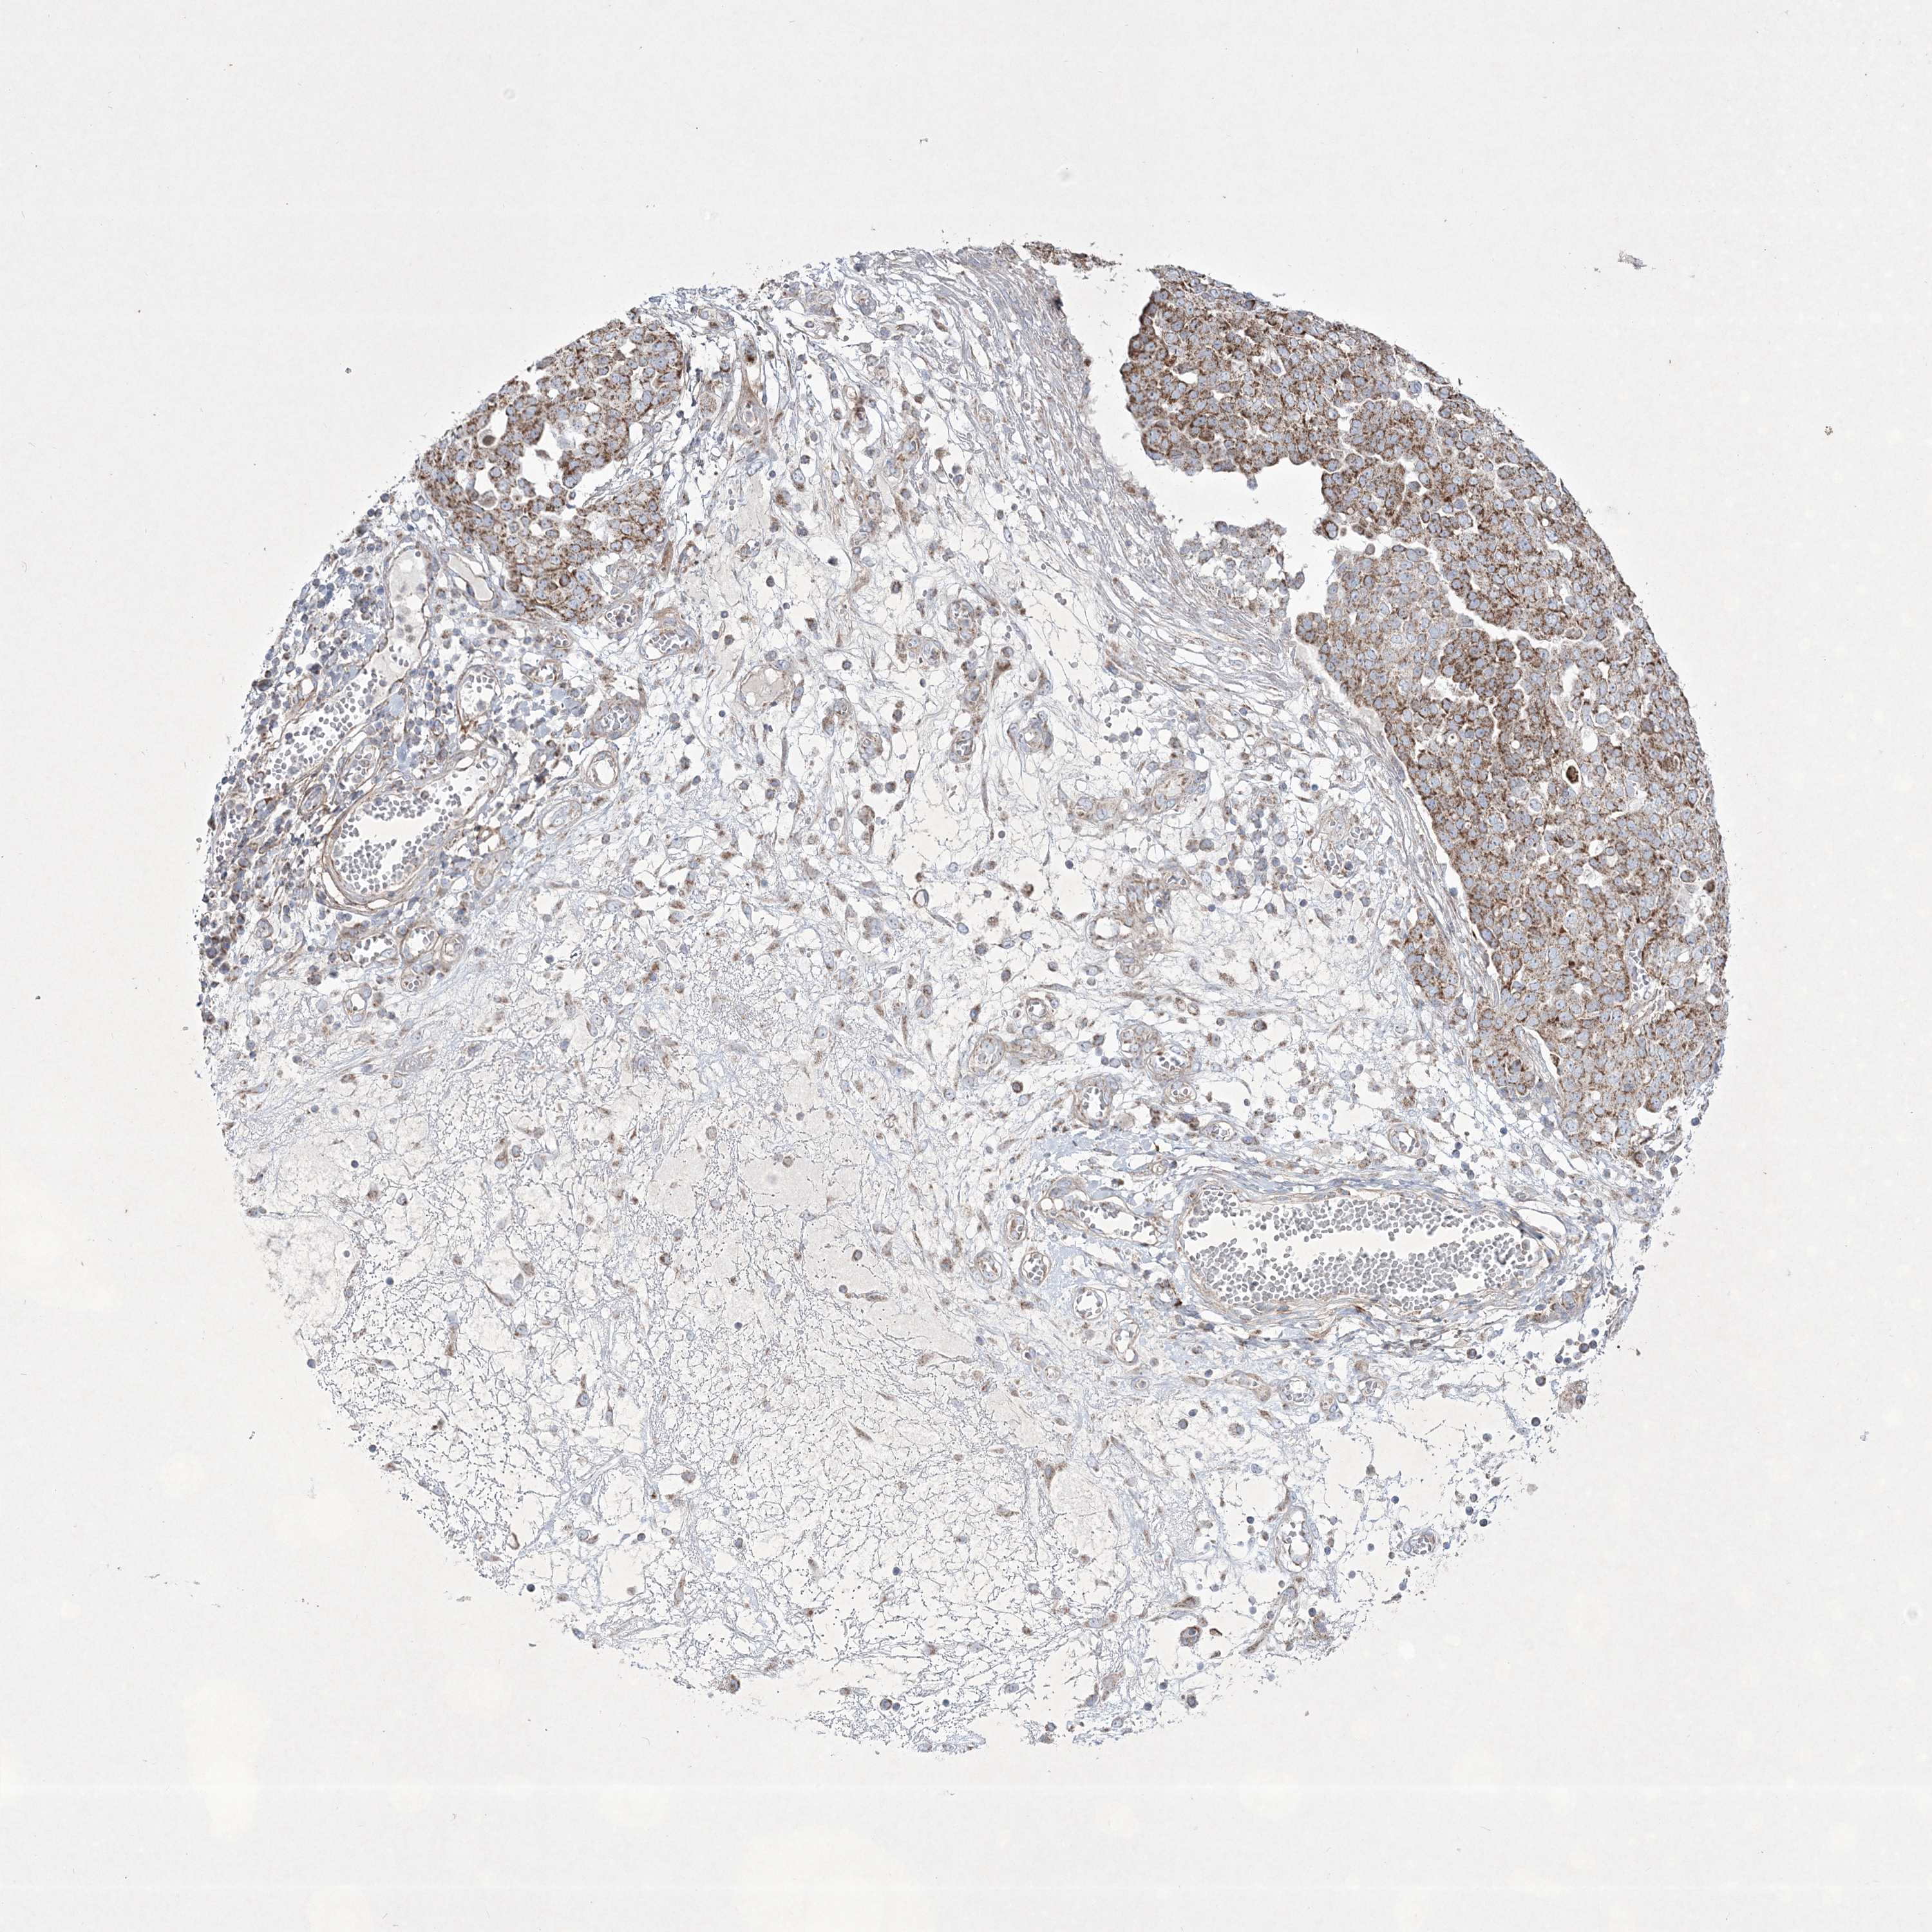

OVARIAN CANCER - Protein expressioni

A mouse-over function shows sample information and annotation data. Click on an image to view it in a full screen mode. Samples can be filtered based on level of antibody staining by selecting one or several of the following categories: high, medium, low and not detected. The assay and annotation is described here.

Note that samples used for immunohistochemistry by the Human Protein Atlas do not correspond to samples in the TCGA dataset.

Antibody stainingi

Antibody staining in the annotated cell types in the current human tissue is reported as not detected, low, medium, or high, based on conventional immunohistochemistry profiling in selected tissues. This score is based on the combination of the staining intensity and fraction of stained cells.

Each image is clickable and will lead to virtual microscopy that enables deeper exploration of all samples and also displays staining intensity scores, fraction scores and subcellular localization as well as patient and tissue information for each sample.

Antibody HPA037802

Antibody HPA037803

Cystadenocarcinoma, serous, NOS

Carcinoma, endometroid

Cystadenocarcinoma, mucinous, NOS

Carcinoma, NOS